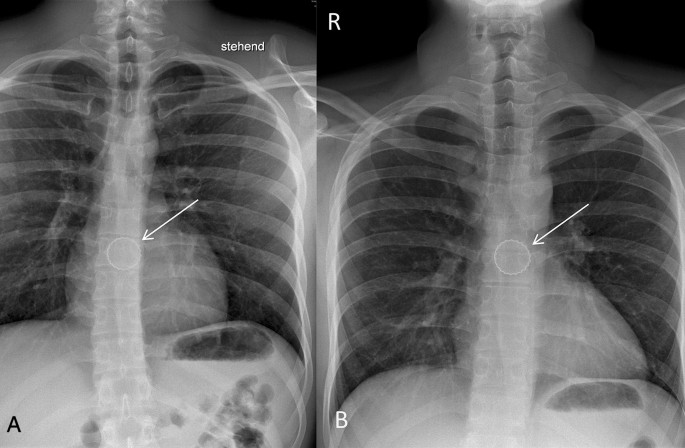

In all patients, there was radiographic proof by chest or neck X-ray of a bottlecap stuck in the esophagus. 10 (71.4%) were localized in the cranial third of the esophagus, 3 (21.4%) were localized in the middle third of the esophagus and 1 (7.1%) was localized in the caudal third of the esophagus (Figs. 1, 2, 3). Interestingly, in all imaging findings, the bottlecap has nearly the same alignment in space, flat parallel to the spine.

Lower esophageal narrowing. It lies at thoracic vertebrae near X/XI in the area of the esophageal hiatus shortly before the esophago-gastral transition. A: Posterior–anterior X-ray of the thorax (A). Bottlecap near thoracic vertebra VII (arrow). B: Posterior–anterior X-ray of the thorax (A). Bottlecap near thoracic vertebra VI/VII (arrow). R right; L Left; a anterior; p posterior